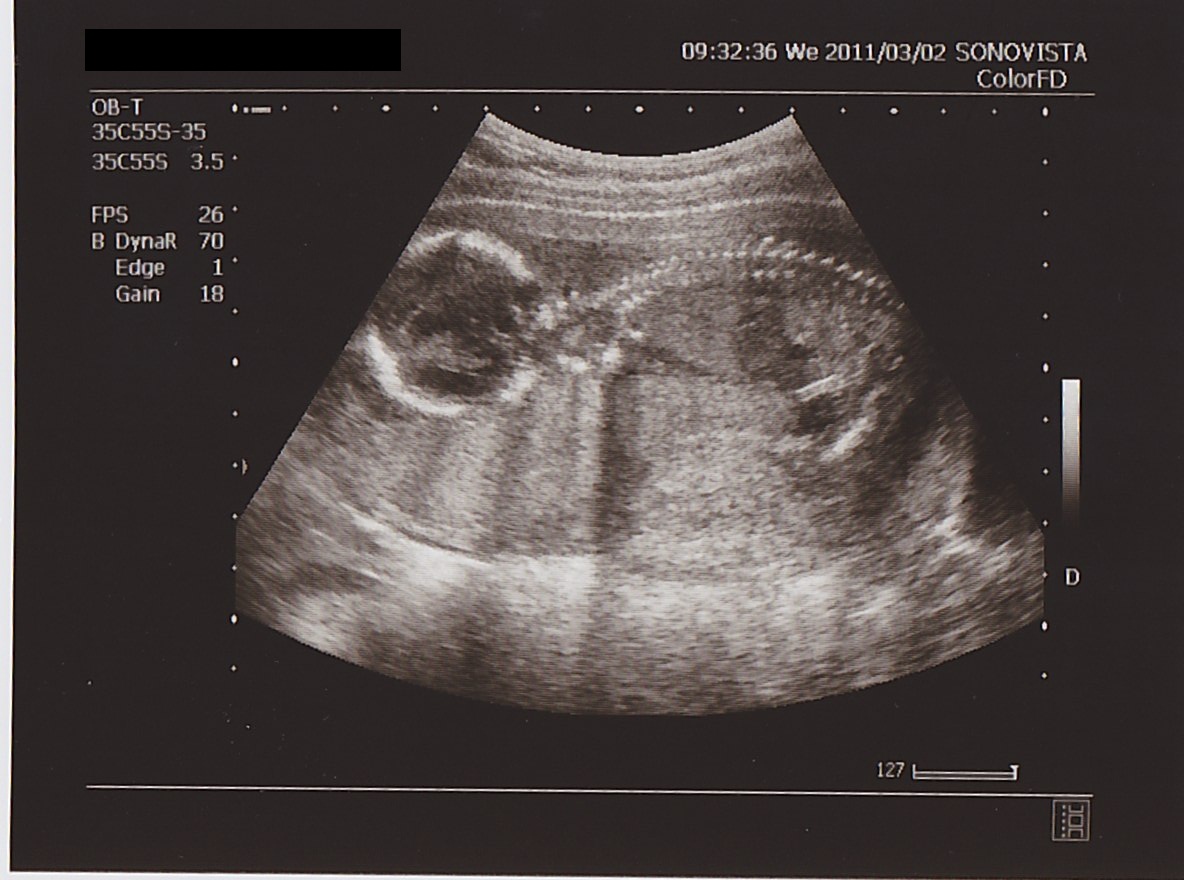

全身像は…

▲ 背骨が シッカリ 映ってる!

下を 向いている 状態。

写真上部の アーチ型が 背骨。

角度を 変えて 見たときは

肘を 曲げて

ほおづえを ついているような 格好をしていました。